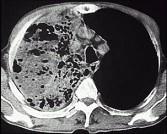

问题 男,30岁,咳嗽咯血,盗汗1个月,伴消瘦无力发热,CT如图,应考虑为 ( )

选项 A.右上肺大叶性肺炎 B.右上肺干酪性肺炎 C.右侧脓胸 D.右上肺多发肺脓肿 E.右上肺不张

答案 B